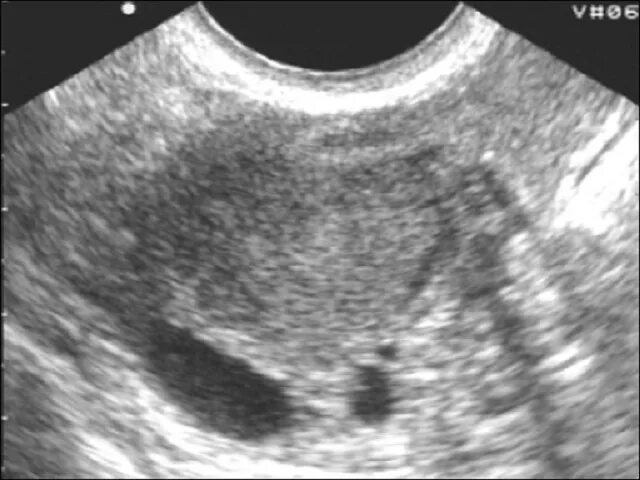

Аденомиоз диффузные изменения